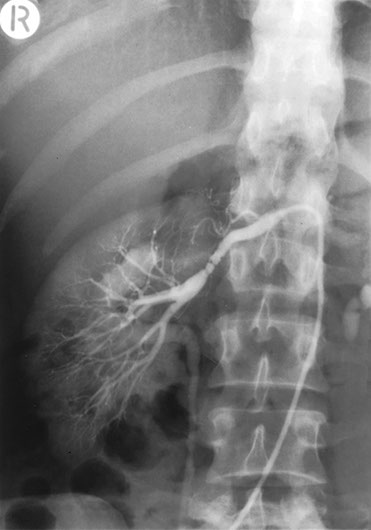

Fibromuscular dysplasia has a beaded appearance of narrowing and dilatation of the vessel wall and should be considered when a young patient presents with hypertension.

On the whole, fibromuscular dysplasia can be satisfactorily treated by balloon angioplasty. However, in this patient, it was not successful and surgical correction by a graft between abdominal aorta and renal artery was carried out.

However, the graft again stenosed as you can see. Fibromuscular dysplasia may affect many arteries and here the arrow is pointing to disease of the right common iliac artery in the same patient.